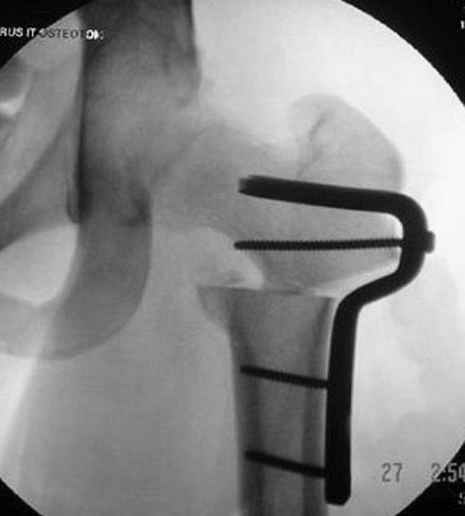

Если, например, доводится лечить больных с псевдартрозами шейки бедра, то надобность есть, и приходится. См. приложение.

Несколько снимков из моей коллекции, чтобы разьяснить, почему мы до сих пор делаем различные варианты остеотомии.

На рисунке N1 предоперационный план лечения ложного сустава шейки бедра- линия ложного сустава, угол и направление введения импланта, клиновидная остеотомия в градусах и миллиметрах, второй снимок после коррекции, расчет, на сколько удлиняется конечность и размеры импланта;

N3 рисунок окончательный снимок, после операции моя рентгенограмма должен выглядеть примерно как эта картина. На N4 снимке клин перед удалением; N5 послеоперации 3 нед.; N6 окончательная рентгенограмма.